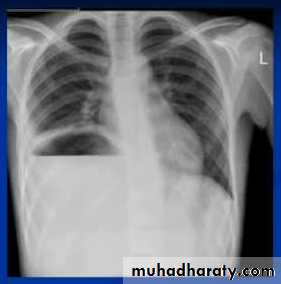

Massive pleural effusion with mediastinal shift to the left.

(A) Chest radiograph

(B) CT coronal reconstruction. A massive effusion displaces the mediastinum to the left. CT shows the important pleural effusion together with the enhanced atelectatic left lung.

Note also the depression of the right hemidiaphragm (arrows).